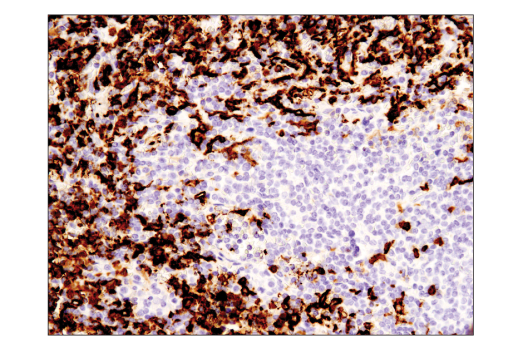

Immunohistochemical analysis of paraffin-embedded normal rhesus monkey spleen using CD16 (D1N9L) Rabbit mAb. Data were generated using the standard formulation of this product.

Immunohistochemistry Image 4: CD16 (D1N9L) Rabbit Monoclonal Antibody (BSA and Azide Free)